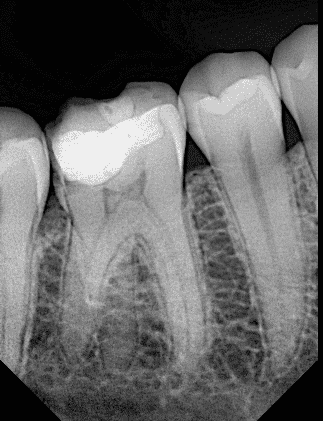

Pre-operative x ray

You can see the liner below the old composite ,irregular margins, mesial wall of the second molar need to be restored

Here you can see that the remaining walls are weak and must reduced and replaced by strong indirect lithium disilicate overlay

The mesial box of the first molar opened and here you can see the remaining walls are indeed very weak